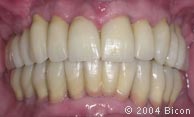

117. | 戴入基台冠后的微笑。 |

133. | 戴入最终修复体2周后病人的微笑。 |

136. | 戴入最终修复体2周后的唇颊侧观。 |

146. | 术后的唇颊侧观。 |

148. | 术后的微笑。 |